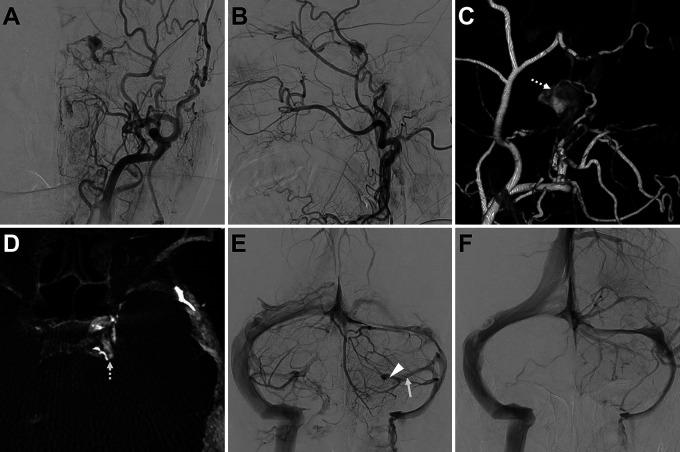

A 74-year-old woman presented with left-sided conjunctival injection and exophthalmos. Cerebral angiography showed a left CS-DAVF draining into the left uncal vein and superior ophthalmic vein, with the fistulous point located in the posterosuperior compartment of the left CS. The left inferior petrosal sinus and internal jugular vein were occluded, and no drainage route from the left superior ophthalmic vein was seen. The anterior segment of the left superior petrosal sinus (SPS) was occluded, but the posterior segment was not. Microangiography from the posterior segment of the left SPS showed a beak-like orifice in the anterior segment of the left SPS toward the left CS. A micro-guidewire was guided through the beak-like orifice, and the microcatheter was advanced into the left CS. The left CS was packed and the DAVF was occluded.

Transvenous embolization through an occluded SPS may be an option in the endovascular treatment of CS-DAVFs. Penetration along the beak-like orifice of the occluded SPS visualized by venography at the blind end of the SPS may be useful in reaching the CS via the SPS.

一名74岁女性出现左侧结膜充血和眼球突出。脑血管造影显示左侧CS-DAVFs引流至左侧钩静脉和眼上静脉,瘘口位于左侧海绵窦的后上部分。左侧岩下窦和颈内静脉闭塞,未发现眼上静脉的引流途径。左侧岩上窦(SPS)前段闭塞,但后段未闭塞。从左侧SPS后段进行的微血管造影显示,左侧SPS前段有一个朝向左侧海绵窦的喙状开口。通过该喙状开口引导微导丝,将微导管推进至左侧海绵窦。对左侧海绵窦进行填塞,闭塞了DAVF。

通过闭塞的岩上窦进行经静脉栓塞可能是CS-DAVFs血管内治疗的一种选择。在岩上窦盲端通过静脉造影显示的沿着闭塞岩上窦的喙状开口进行穿刺,可能有助于通过岩上窦到达海绵窦。